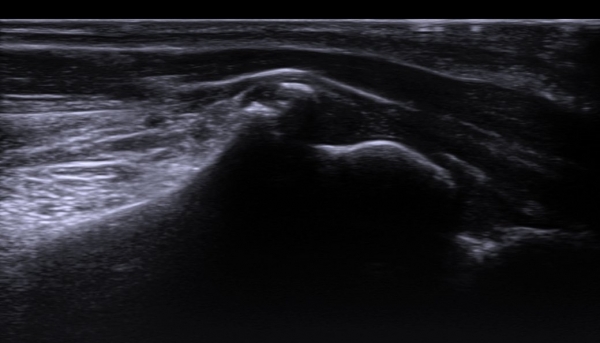

±ÙÀüµµ  °Ë»ç  : ¼ö±Ù°ü ÁõÈıº¿¡ ºÎÇÕÇÏ´Â Á¤Á߽ŰÜÀÇÀÇ ¼Û¸ñºÎÀ§¿¡¼­ º´Áõ

ÃÊÀ½ÆÄ  °Ë»ç  : Á¤Á߽Űæ Á¾´Ü¸é°Ë»ç¿¡¼­ Á¤Á߽ŰæÀÌ ¼Õ¸ñ ºÎÀ§¿¡¼­ °ñ±Ø¿¡ ÀÇ ±¹¼ÒÀû ¾Ð¹ÚÀ» º¸ÀÌ°í ¾Ð¹Ú ±ÙÀ§ºÎ¿Í

¸»´ÜºÎ¿¡¼­ Á¤Áõ½Å°æÀÇ Àú¿¡ÄÚ ºÎÁ¾ÀÌ ¶Ñ·ÇÇÏ´Ù(»çÁø 1).

ÀÌ °ÍÀº Ư¹ß¼º ¼ö±Ù°üÁõÈıº¿¡¼­ ¾Ð¹ÚºÎÀ§±â ¼ö±Ù°ü ¸»´ÜºÎÀÎ Á¡°ú ´Ù¸¥ ¼Ò°ßÀ¸·Î ¼ö±Ù°ü ÁõÈıºÀÇ

¿øÀÎÀÌ ¼Õ¸ñ¿¡¼­ °ñ±Ø¿¡ ÀÇÇØ ¹ß»ýÇÑ °ÍÀÓÀ» ½Ã»çÇÏ´Â ¼Ò°ßÀÌ´Ù.